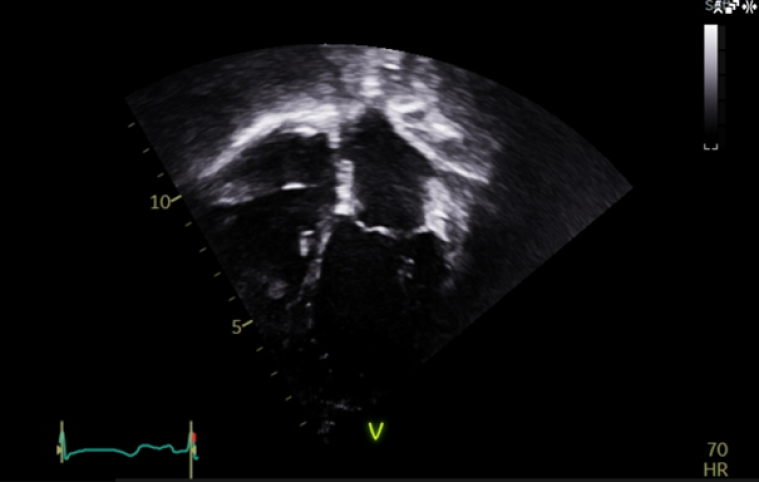

At the age of 4 years, the patient started developing a distinct echocardiographic phenotype (Image 5), with a dilated left atrium (LA) (LA area 12.1 cm3, z score +5.7) and right atrium (RA) (RA area 10.8 cm3, z score +4.1), preserved global left ventricular systolic function, but impaired longitudinal function (tissue doppler lateral S’ wave 0.07m/s, septal 0.05m/s) and evidence of early impaired left ventricular relaxation (isovolumetric relaxation time 114ms, pulmonary vein A-wave duration 166msm abnormal mitral valve doppler). The left ventricle itself was normal in size, with a maximal wall thickness of 5-6mm (z score +02), with no significant valvular or other abnormalities.

CC Vol 10 Picture5_escardio-Clinical case.png